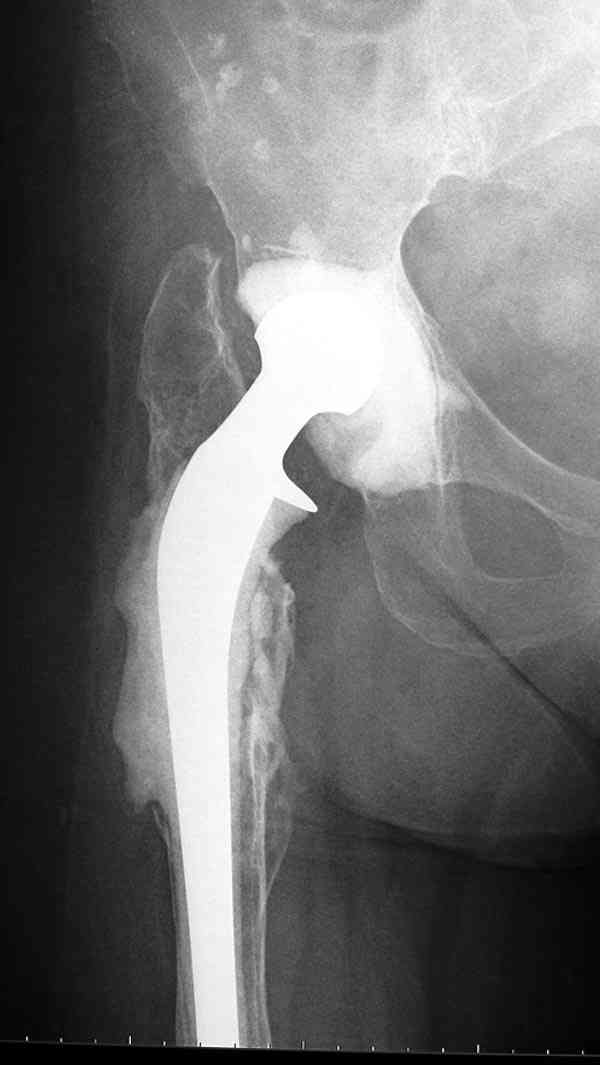

Недавно на сайте выставлял случай восьмилетнего наблюдения после инфицированного эндопротезирования, кроме ножки из цемента с антибиотиком также был сооружен и ацетабулярный компонент.

Так что вместе ожидания, можно было бы рассмотреть предлагаемый вариант, потом, если это возможно было бы интересно посмотреть на рентгенологическую картину.